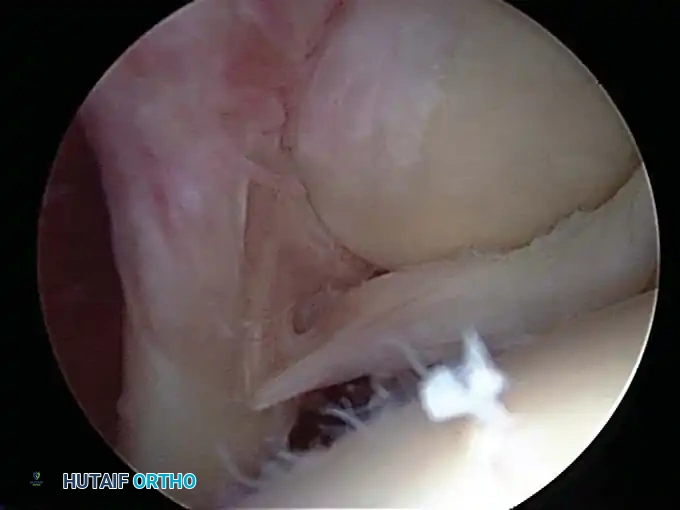

Early identification of micro-instability is paramount. Subtle instability often precipitates superior labral anterior and posterior (SLAP) lesions and secondary rotator cuff impingement. By identifying these lesions early, treatment can be directed at the root biomechanical cause rather than merely the secondary symptoms.

In the overhead throwing athlete, the shoulder is repeatedly placed in extreme abduction, hyperextension, and external rotation (the late cocking phase). This position forces the greater tuberosity and the undersurface of the rotator cuff to impinge against the posterosuperior glenoid rim and labrum. This internal impingement results in fraying of the cuff undersurface and the superior labrum. Repetitive microtrauma leads to anteroinferior ligamentous laxity and a "peel-back" of the posterosuperior capsular complex.

Appropriate surgical intervention relies on a thorough arthroscopic evaluation to decode these complex pathological findings. Diagnostic arthroscopy is also highly indicated for:

* Identification and extraction of loose bodies: Particularly those residing in the posterior recess, which are notoriously overlooked during open procedures.